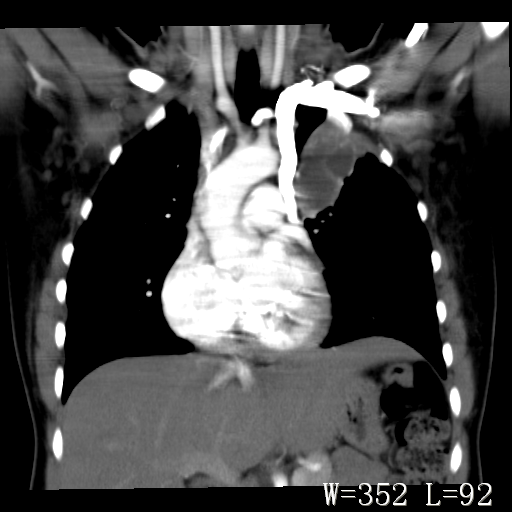

标题: CT27017:1、肺结核?2、永存左上腔静脉。

女,32岁,自述肺结核治疗多年复查。

1)考虑左肺上叶肺脓肿,节段性肺不张。2)永存左上腔静脉。

1)考虑左肺上叶节段性肺不张。原因?2)永存左上腔静脉。

支持肺脓肿;还是双上腔静脉确切些吧,回流至冠状窦或右心房。

考虑左肺上叶胸腺瘤可能性大。肺不张/永存左上腔静脉

1、胸骨后偏左侧囊实性病灶,考虑胸腺瘤可能性大。2、永存左上腔静脉。